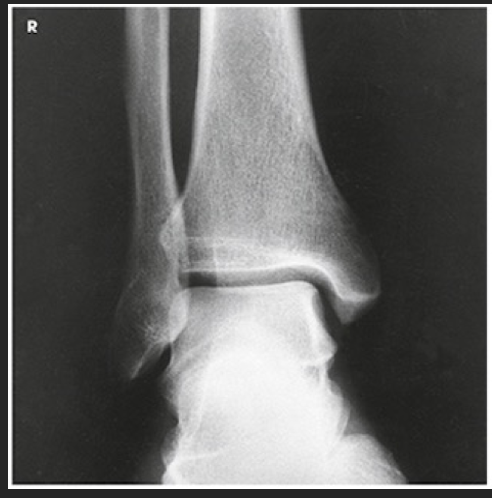

Name this projection.

AP oblique mortise joint

State the degree and type of rotation used.

15-20 medially